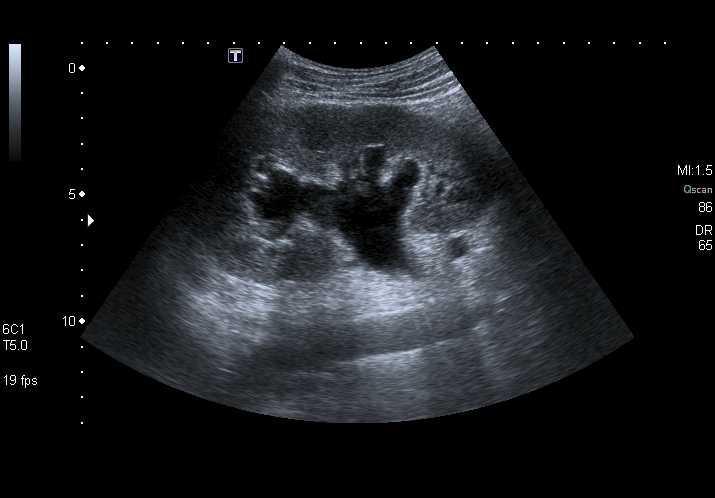

Hydronéphrose sévère

-

Dilatation majeure, calices largement ouverts

Amincissement du parenchyme rénal

Rein globuleux, architecture altérée

![]()

Hydronéphrose sévère. © POCUS Atlas

➡️ Plus l’hydronéphrose est marquée, plus l’obstruction est significative ou prolongée.